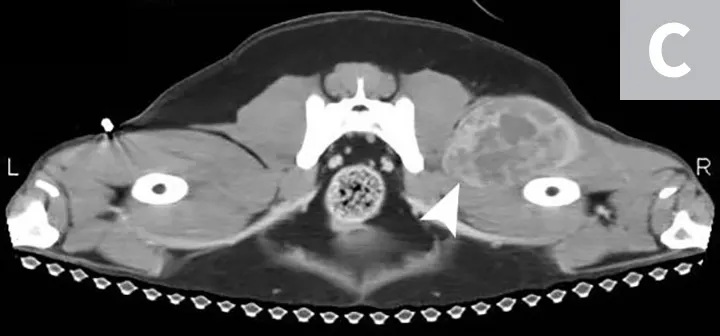

Although HSA can be presumptively diagnosed based on multiple clinical and physical findings and patient signalment, baseline diagnostic tests (see Baseline Diagnostic Tests) should be considered in patients that have probable HSA. Detailed images of HSA lesions arising from visceral organs, SC tissue, and deeper muscle structures can be acquired with advanced imaging modalities (eg, CT; Figure 3).

CT images of primary splenic HSA (A, arrowhead), SC HSA (B, arrowhead), and deep-muscle HSA (C, arrowhead). Figures courtesy of Louis-Philippe de Lorimier, DVM, DACVIM (Oncology)